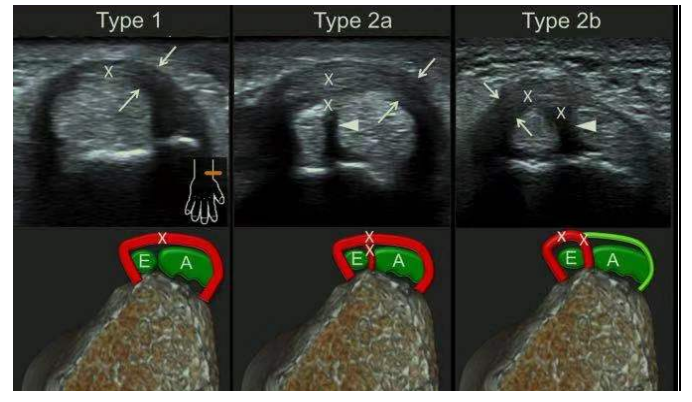

超聲還能有效鑒別拇長展-拇短伸肌腱腱鞘內(nèi)有無解剖變異,是否存在纖維間隔,常見的解剖變異有兩型:部分型纖維間隔(2a)和完全性纖維間隔(2b)

Type1型是正常人群第一腔室解剖特點(diǎn),沒有解剖變異,拇長展-拇短伸2根肌腱被共同的腱鞘包繞在第一腔室內(nèi),炎癥累及第一腔室腱鞘;Tpype2a型是第一腔室內(nèi)存在纖維間隔,但纖維間隔是部分性的,它將拇長展-拇短伸2根肌腱部分分隔開,炎癥累及第一腔室腱鞘及纖維間隔;Tpype2b型是第一腔室內(nèi)存在完全性纖維間隔,纖維間隔將拇長展-拇短伸2根肌腱完全分隔開,但炎癥僅累及拇短伸肌腱腱鞘及其纖維間隔。